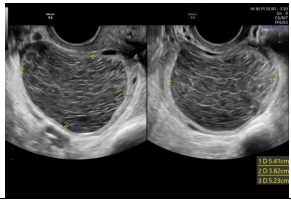

Paciente de 32 anos com infertilidade primaria há 3 anos, ciclos menstruais regulares, sem dispareunia, sem dismenorreia, realiza ultrassom transvaginal no 23 dia do ciclo menstrual, identificando a seguinte imagem anexial.

A imagem ecográfica sugere como diagnóstico

Paciente de 32 anos com infertilidade primaria há 3 anos, ciclos menstruais regulares, sem dispareunia, sem dismenorreia, realiza ultrassom transvaginal no 23 dia do ciclo menstrual, identificando a seguinte imagem anexial.

A imagem ecográfica sugere como diagnóstico